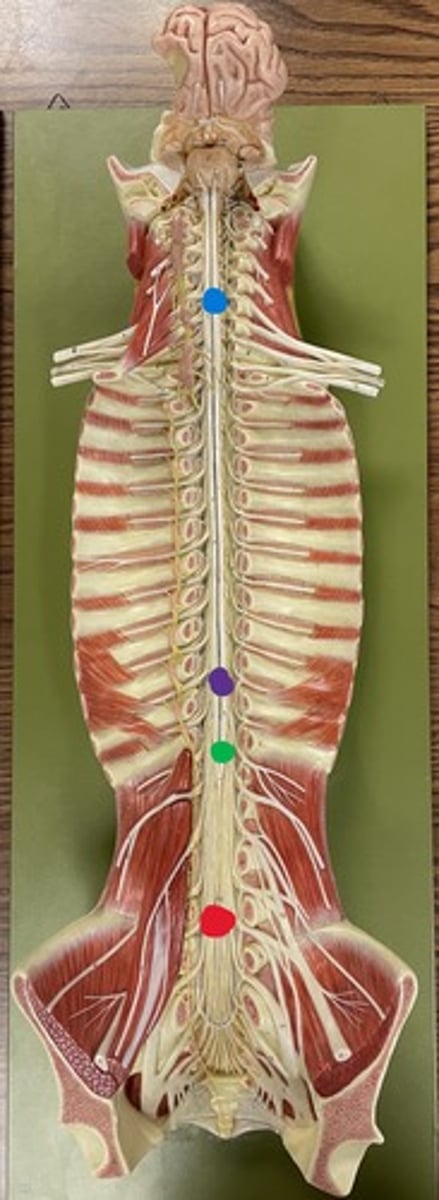

Cervical enlargement

Blue

Lumbar enlargement

Purple

Conus medullaris

Green

Cauda equina

Red

Filum terminale

blue